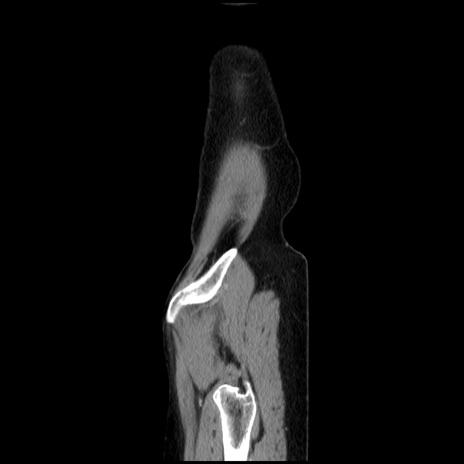

横断像

【症例】40歳代 女性

【主訴】上腹部痛、嘔気・嘔吐

【現病歴】約9時間前頃から急に上腹部痛、嘔気、嘔吐が出現。改善しないため救急要請。

【既往歴】子宮頚癌(広汎子宮全摘術、放射線療法)、腸閉塞

【身体所見】腹部:平坦、軟、腸雑音亢進、上腹部を中心に腹部全体に圧痛あり。

【データ】WBC 8400、CRP 0.03